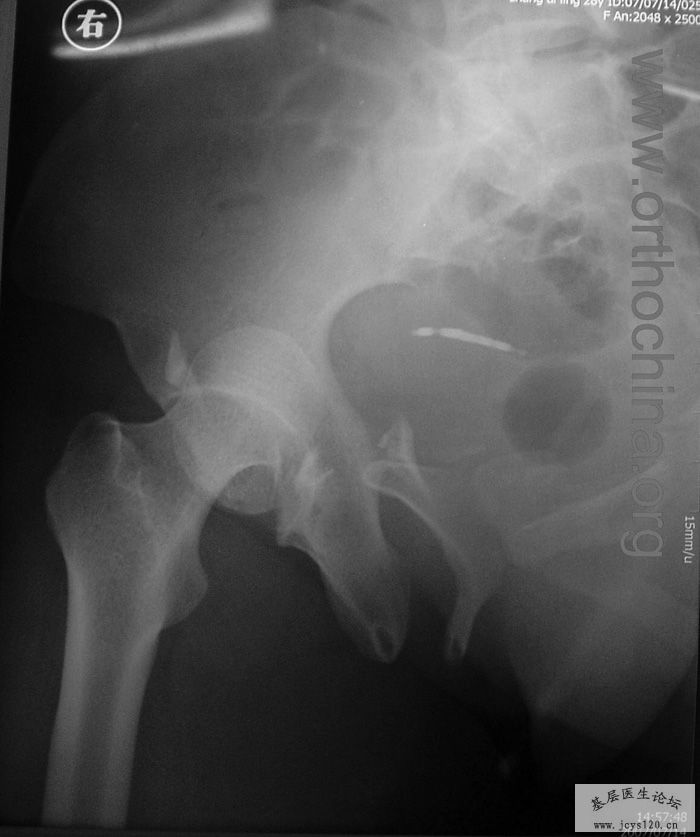

患者,女,28岁,车祸中骨盆轧伤后疼痛功能障碍1小时。查体:休克外貌,烦躁不安。头颈胸腹无异常,脊柱无异常,两下肢血供及感觉正常。骨盆挤压分离试验阳性。阴道、尿道、直肠、腹内脏器无损伤。住院后抗休克、骨牵引及对症治疗1周后,行前后联合入路手术。股骨头骨折复位后用可吸收螺钉固定,骶髂关节、髋臼前后柱、对侧耻骨上下支用骨盆重建钛板固定,术中出血1200ML,手术时间8小时。部分图片如下: